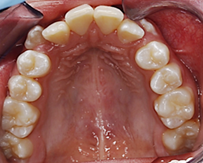

Fotografía oclusal superior: Forma de arcada ovoide, apiñamiento en el sector anterior, palatinización de las piezas 1.2 y 2.2, piezas 1.3 y 2.3 ectópicas, paladar profundo (D). Fotografía oclusal inferior: Forma de arcada oval, lingualización de las piezas 4.5 y 4.6, ausencia de la pieza 3.7 (E). Fotografía de resalte: La sobremordida horizontal y vertical de -2 mm (F).